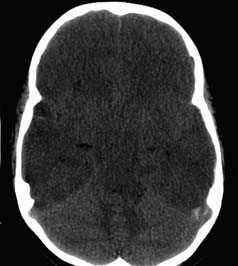

б - Транстенториальное вклинение среднебазального отдела височной доли, вызванное большой острой субдуральной гематомой. Типичная КТ больного с вклинением миндалин мозжечка а - Диффузный супратенториальный отек головного мозга у маленького ребенка.

Обратите внимание на гиподенсную супратенториальную часть мозга по сравнению с наметом и инфратенториальным пространством.

б - Острая окклюзионная гидроцефалия у маленького ребенка. Это осложнение развилось в течение 6 часов после первой КТ.